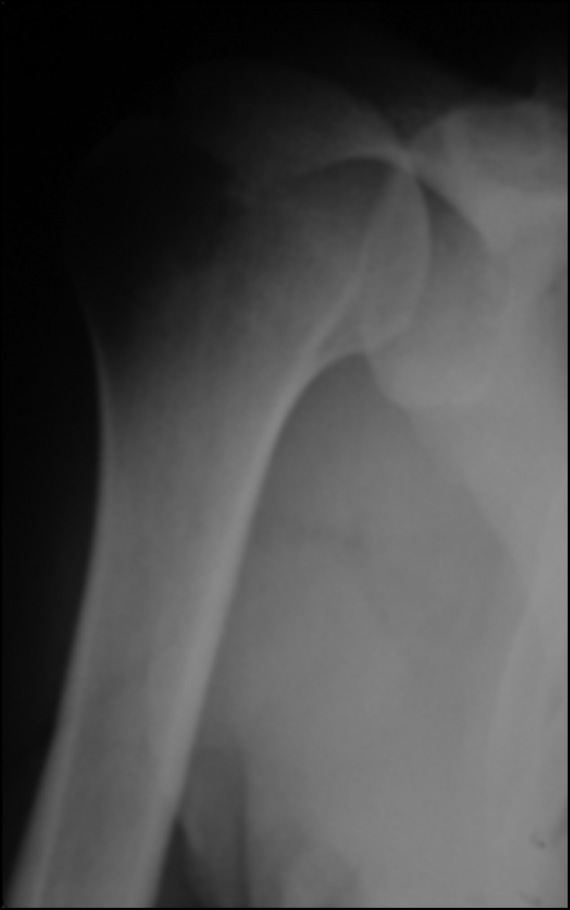

All patients underwent a thorough preoperative clinical examination, magnetic resonance imaging (Fig. 1), computed tomography (Fig. 2), and radiography of the shoulder joint in the antero-posterior, West Point and Stryker views (Fig. 3) [17, 24].

Fig. 3. Radiography of the shoulder joint before arthroscopic Latarjet surgery.